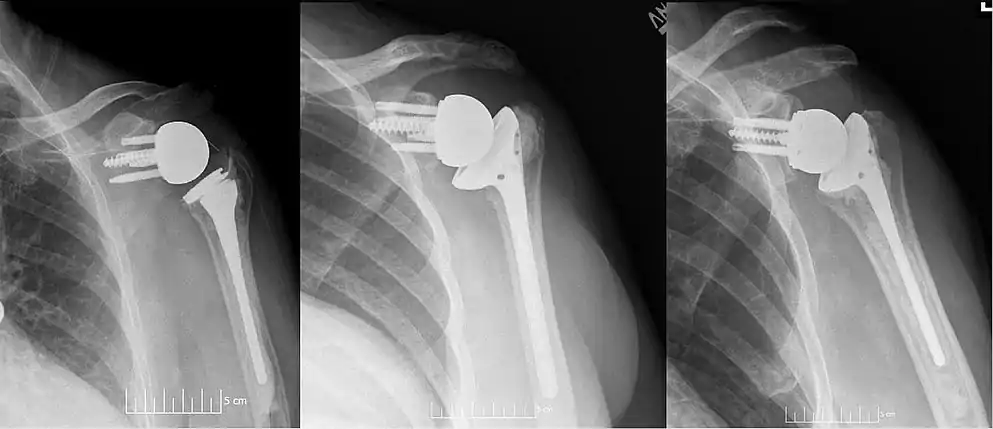

Plain film radiograph in anteroposterior (AP) view of a right shoulder status post reverse shoulder arthroplasty using a prosthesis with a lateralized center of rotation.

Plain film radiographs in anteroposterior (AP) view of left shoulders that are status post reverse shoulder arthroplasty using three design iterations each with a 135-degree neck-shaft angle and lateralized center of rotation.